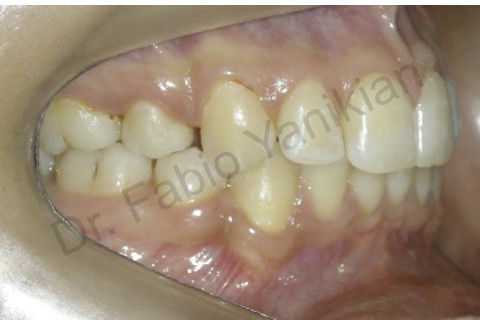

Foto lateral direita final

Foto lateral esquerda final

Paciente CL I com apinhamento superior e inferior

Evolução clínica: exo dos 4 prés, alinhamento e nivelamento, não foi necessario fazer RAS e RAI mas perda de ancoragem nos 4 quadrantes para fecar os espaços.